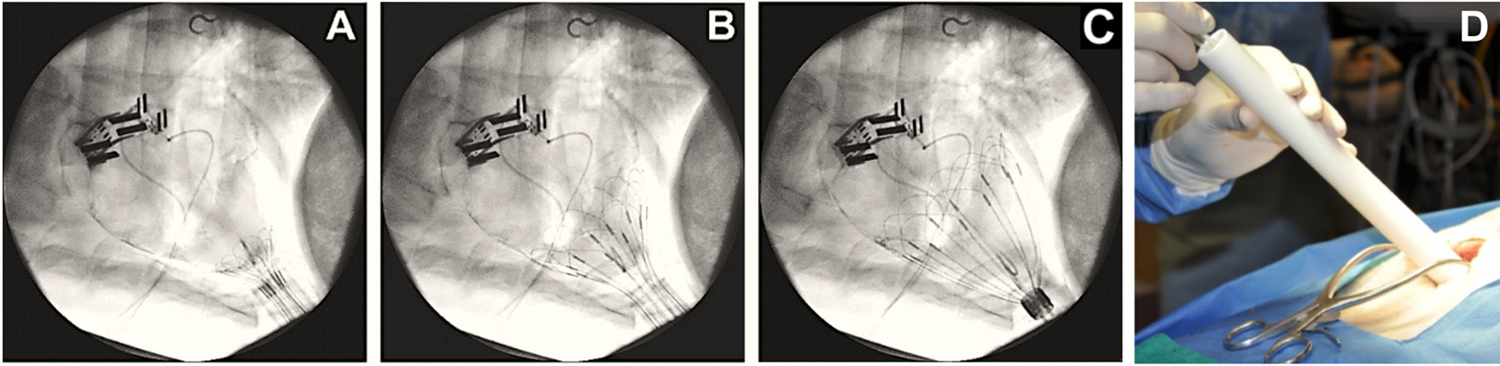

Minimally invasive placement is an important and underappreciated advantage of the CorInnova device, which in animals is inserted through a small subxiphoid incision and opening at the apex of the pericardium (Fig. 8, Ref. [44]). In humans, the approach being developed begins with a minithoracotomy over the cardiac point of maximal impulse, followed by a completely catheter-based insertion guided by echocardiographic visualization of the pericardial sac. Minimally invasive placement allows the pericardial sac to remain intact. An intact pericardium stabilizes the device in an appropriate position without the need for cardiac anchoring sutures, and it also should prevent the heart from being pushed out of the device when the device compresses the heart [48]. This eliminates the anchoring challenges observed with the Anstadt Cup, Acorn CorCap, and dynamic cardiomyoplasty [50].

Fig. 8.CorInnova device delivery. (A–C) Fluoroscopic images

showing use of the deployment tube and self-deploying wire frame to successfully

place the device in the pericardial sac. (D) The surgeon pushes the device out of

the delivery tube and into the pericardial sac. Deployment with this method has a

success rate of 100% to date and an average placement time of